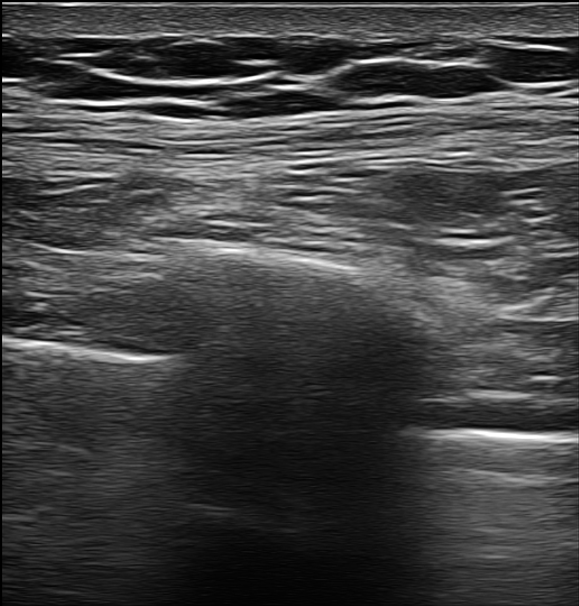

저희는 SI(초음파유도하)주사 치료라고 부르고 있습니다.

영상 장비를 활용해 정확한 병변 위치에 주사를 놓는 거죠.

저희 콕병원에서는 초음파를 통해 실시간으로 보면서 직접 확인하며 진행합니다.

신경 위치, 바늘 깊이, 약물 주입 경로…

모든 걸 눈으로 보면서 하는 거죠.

그림7.png <사진에서 잘 보이실지 모르겠습니다. ^^ 진단 후 주사를 통해 치료하는 영상입니다.>

이게 SI치료의 핵심입니다.

환자분께도 자세히 설명드렸습니다.

"초음파로 신경 위치를 정확히 보면서 할 거예요.

제가 직접 다 확인하면서 진행하니까 안심하세요.

시술 시간도 길지 않고요."